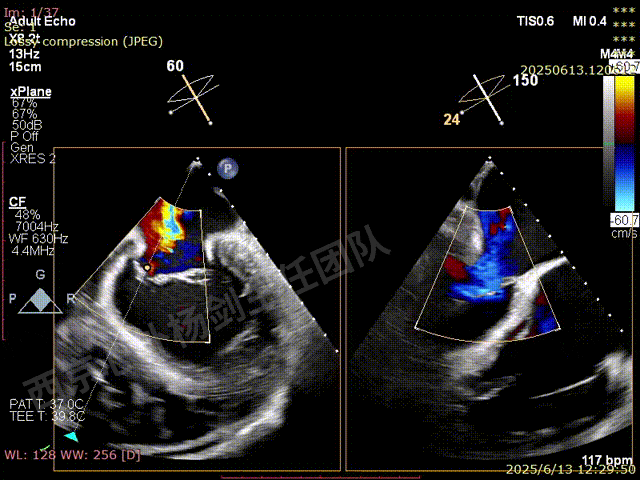

TAVR术后,全心增大,二尖瓣反流重度,三尖瓣反流重度。中量心包积液。左室严重增大,标准图像调整困难。主动脉瓣位带支架人工瓣膜瓣叶启闭正常,主动脉瓣位人工瓣上血流速度Vmax 148cm/s,PGmax 9mmHg,Vmean 86cm/s,PGmean 2mmHg, VTI 34.7cm,瓣周反流(轻)。估测肺动脉收缩压约49mmHg;左室收缩功能明显减低。LVEF:23%,EDV:364ml,ESV:221ml。

彩色血流示:二尖瓣反流缩流颈彩宽6.6mm,面积17cm²,容积30ml;二尖瓣瓣口面积6.6cm²,瓣环内径:左右径34mm,前后径34mm。2区瓣叶长度:前叶36mm,后叶20mm,叶环比1.6. 三尖反流面积17.2cm²,容积33ml,Vmax 291cm/s,PGmax 34mmHg。